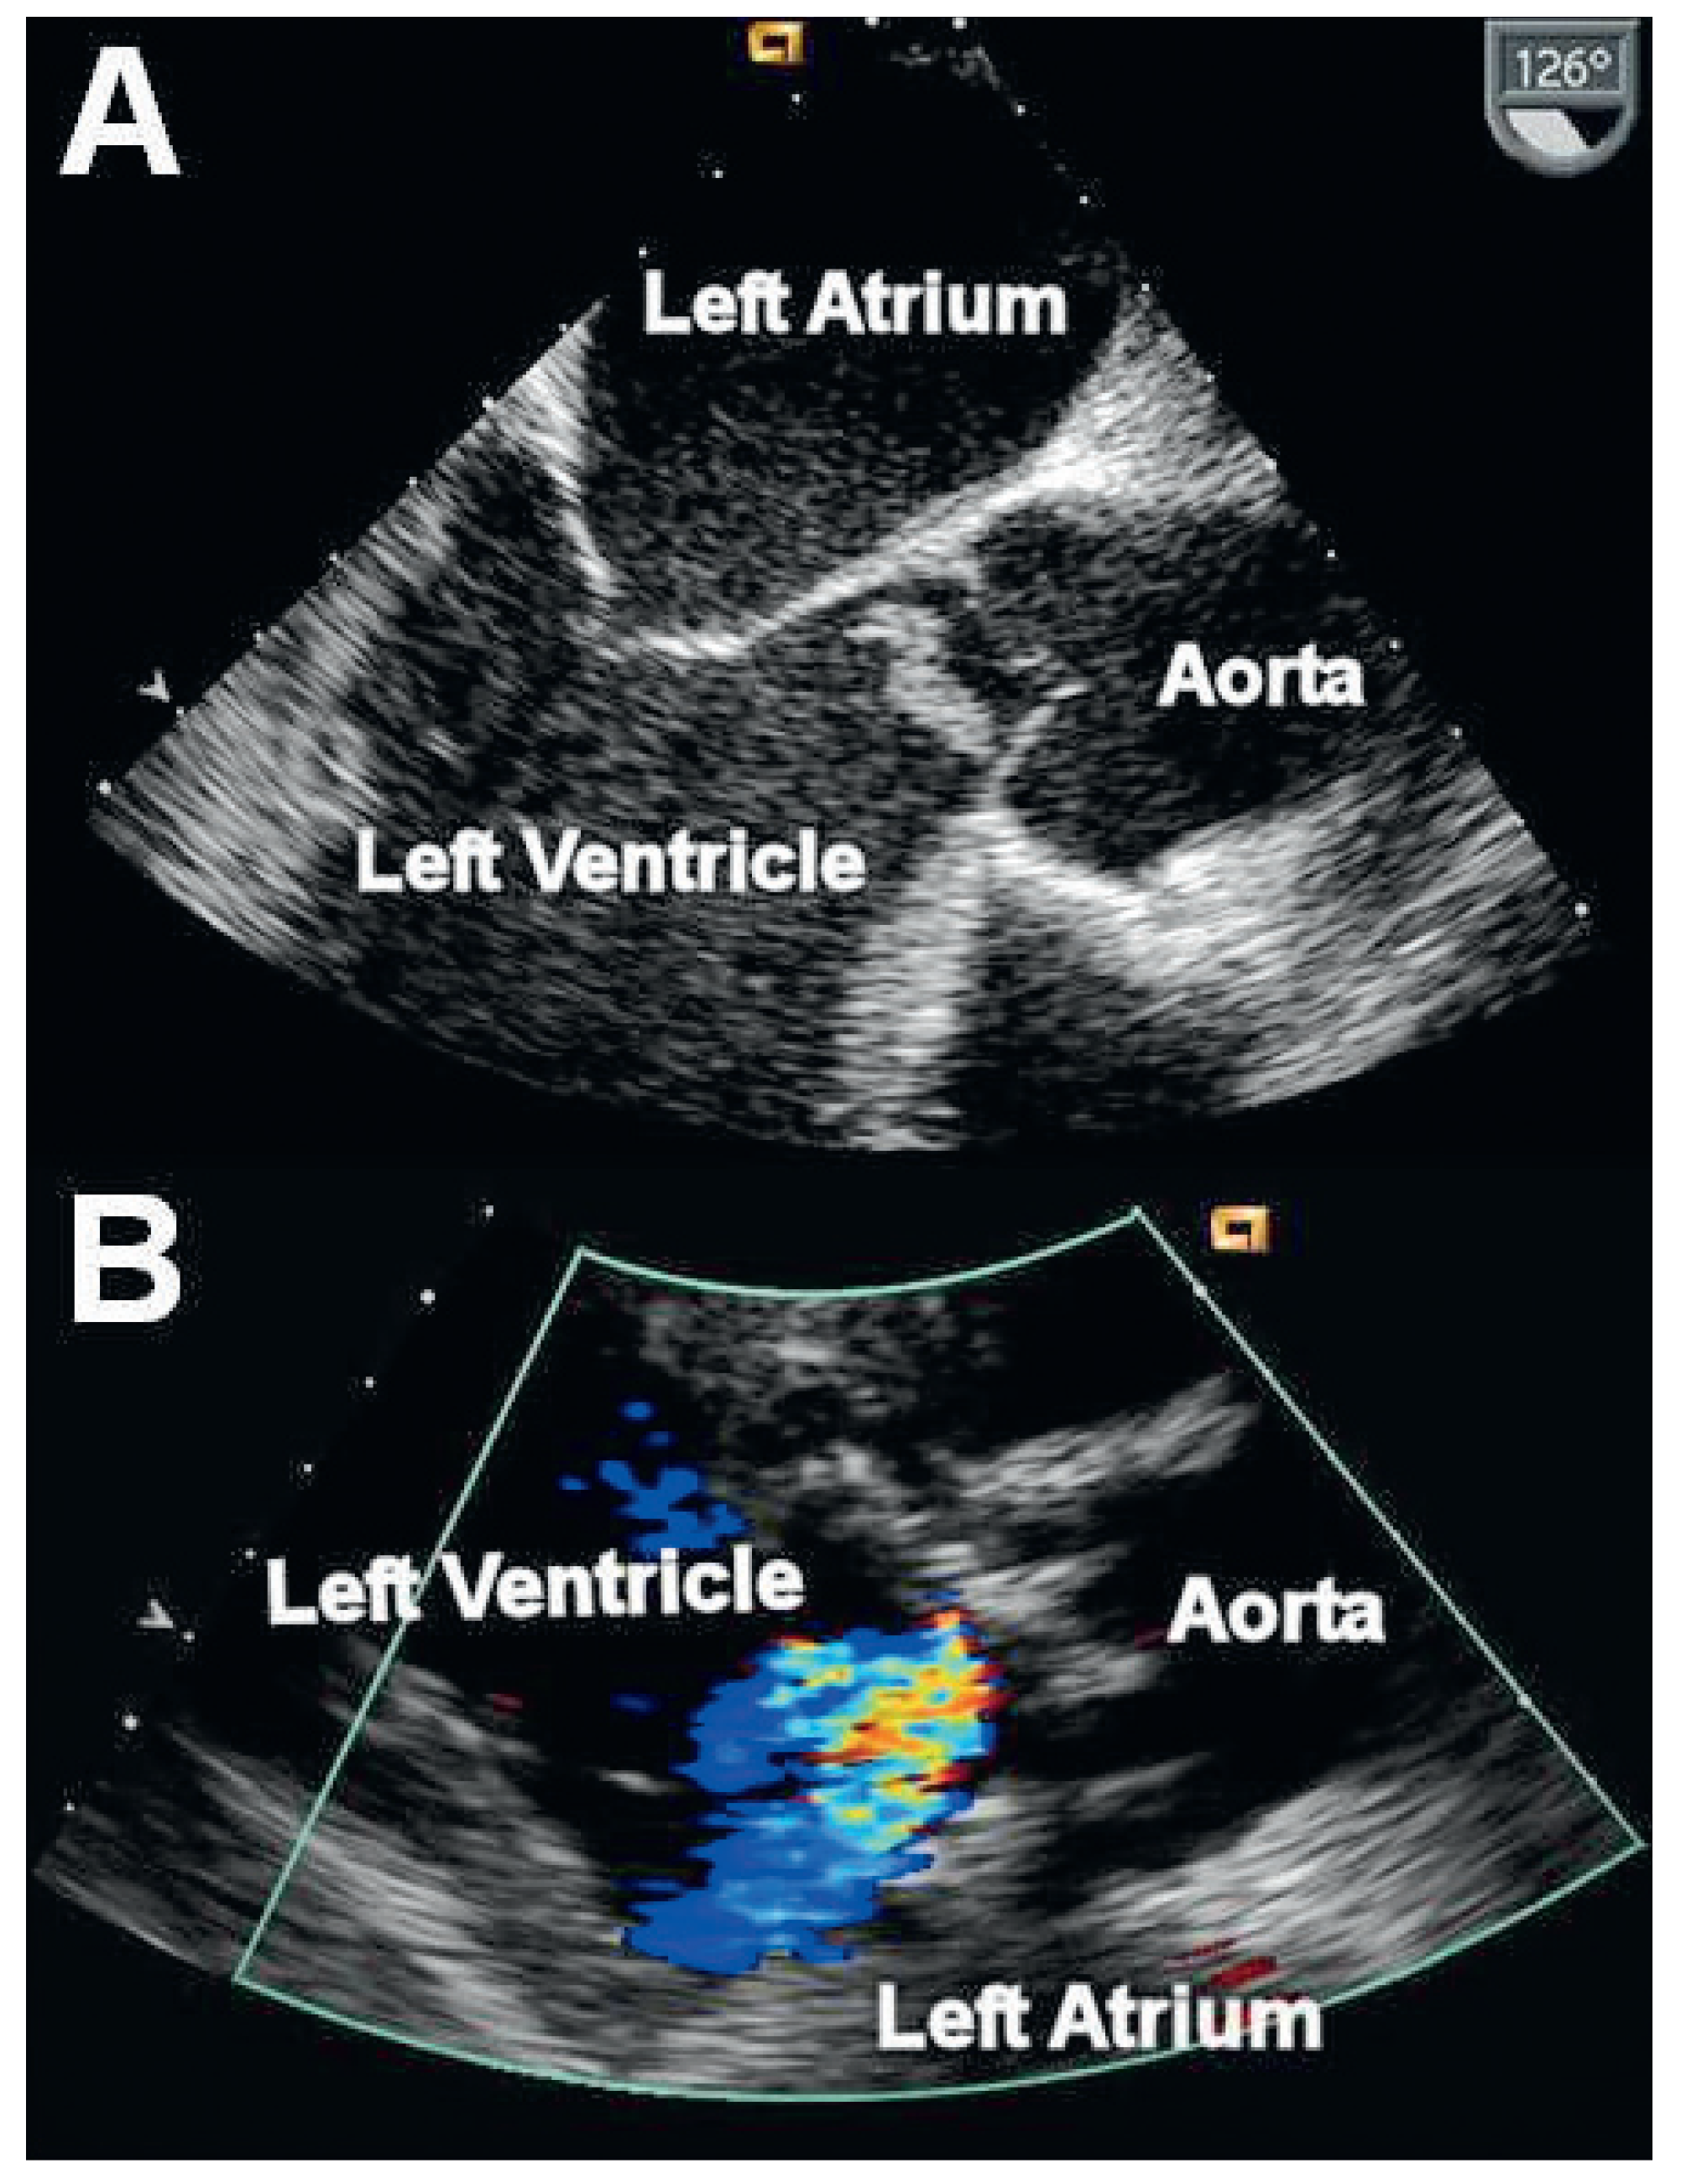

A 44-year-old patient of Serbian origin was admitted to the emergency department with severe dyspnoea, which had begun three days earlier. The patient was suffering from Behçet’s disease treated with methotrexate, prednisone and colchicine. Clinical examination revealed signs of decompensated heart failure and chest X-ray confirmed pulmonary oedema. The patient was intubated, mechanically ventilated and urgently transferred to our hospital. Transoesophageal echocardiography showed severe aortic regurgitation due to a destroyed non-coronary cusp and a large mobile vegetation (Figure 1A). Laboratory tests showed leucocytosis of 19.5 G/L, elevated C-reactive protein (53.7 mg/L) and an accelerated blood sedimentation rate (84 mm/h). The body temperature was 39 degree Celsius. Infective endocarditis was suspected, blood cultures were drawn and empiric antibiotic therapy was initiated. Due to refractory cardiogenic shock, urgent surgical replacement of the aortic valve (bioprosthetic Edwards Perimount Magna Ease valve) was performed. Intraoperatively the non-coronary cusp was found to be destroyed with a big vegetation attached to it. Adjacent to the destroyed cusp the surgeon found a small cavity, presumably an abscess of the aortic root. Therapy for Behçet’s disease was continued as described above.

Blood cultures and serological tests for microorganisms associated with infective endocarditis remained negative. The retrieved vegetation was of a non-specific inflammatory nature and eubacterial polymerase chain reaction of the specimen was negative. Antibiotic therapy with amoxicillin, clavulanic acid, rifampicine and gentamicin was administered for four weeks while immunotherapy for Behçet’s disease remained unchanged. Two months after replacement of the aortic valve, while the patient had more or less recovered, he presented to the emergency department again because of progressive dyspnoea over a few days. Transthoracic echocardiography showed a well functioning aortic valve prosthesis with trivial transvalvular but severe paraprosthetic regurgitation (Figure 1B). Inflammatory markers, including C-reactive protein (44 mg/L) and leukocyte count (18.1 G/L), were again markedly elevated. Six blood cultures were drawn, but remained sterile. A new working hypothesis assuming Behçet-associated aortitis mimicking infective endocarditis was proposed [1,2,3]. Hence, immunosuppressive therapy with high doses of prednisone, azathioprine and infliximab was begun without any additional antibiotics. Inflammatory markers normalised within one week of treatment. Due to the severity of the paraprosthetic regurgitation a conservative approach, as previously described [1], could not be pursued. After two weeks of intensified immunosuppressive therapy, elective surgical aortic root and valve replacement was performed using a mechanical composite graft (ATS Medical). Sutures were reinforced with a xenopericardial layer to prevent recurrent leakage. Histopathological examination of the excised aorta (Figure 2A/B) showed chronic aortitis characterised by dense fibrosis, small collections of lymphocytes and plasma cells, disintegration of elastic lamellas and stenotic vasa vasorum. Furthermore fragmented and thinned elastic fibres in the tunica media were documented [4]. These findings are compatible with Morbus Behçet associated aortitis, although overlapping morphological features are found in different aortic diseases (e.g., Takayasu, syphilis).

Figure 1. (A) Mobile vegetation in the left ventricular outflow tract attached to the non-coronary cusp (transoesophageal echocardiography). (B) Severe paraprosthetic aortic regurgitation (yellow-blue flow) seen on transthoracic echocardiography in the parasternal long axis view.